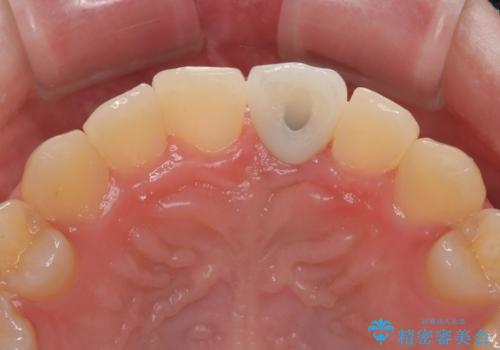

- 前歯のインプラント治療を希望して来院された患者様です。

小学生の時に前歯を殴打したとのことで、歯根が吸収してしまい、抜歯が必要と判断されました。

抜歯、インプラント埋入、仮歯の装着が同時に可能な1DAYインプラントを行いたいところでしたが、吸収による歯肉の炎症が著しいため、抜歯後に炎症が治まるまで待機し、極力早期にインプラント埋入を行うこととしました。